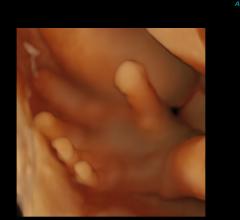

Zonare Medical Systems is showing its recently introduced ZS3 ultrasound system at the annual American Institute of Ultrasound in Medicine (AIUM) meeting April 7-9, 2013 in New York.